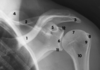

Clinical Limb Joints Flashcards

Identify these parts

1- clavicle

2- scapular spine

3- acromion

4- scapula superior angle

5- coracoid process

6- glenoid fossa

7- humerus head

8- greater tubercle

9- lesser tubercle

10- surgical neck

11- infraglenoid tubercle

12- supraglenoid tubercle

X-ray: #6 = glenoid fossa, #7= head of humerus

4 on xray

5 on xray

xray: #s 8 and 9

10 on xray